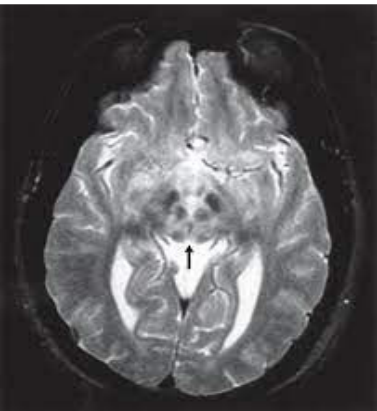

Considere a figura a seguir, que apresenta uma imagem de ressonância nuclear magnética (RNM) com alteração típica no encéfalo, para responder a esta questão.

SONAM, K.; BINDU, P.S.; GAYATHRI N. et al. The “double panda” sign in Leigh disease. Journal of Child Neurology. 2014, v. 29, n. 7, p. 980-982.

I. O diagnóstico da doença de Wilson não pode baseado apenas nesta imagem.

II. O sinal do panda gigante pode estar presente na sarcoidose e síndrome de Leight.